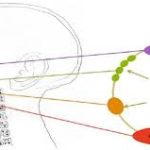

İşte peiatrik adenoid hipertrofisi ve orta kulak ventilasyonu ilişkisini gösteren metin tabanlı şema:

Açıklama:

Adenoid hipertrofisi Östaki borusunu mekanik olarak tıkar.

Tıkanma, orta kulakta negatif basınca yol açar.

Negatif basınç, orta kulakta sıvı birikmesine (otitis media effüzyon) sebep olur.

Kronik durumda işitme kaybı ve tekrar eden orta kulak enfeksiyonları görülebilir.

Bu şema ile hem anatomik hem de fizyolojik farkları net bir şekilde görebiliyorsun: çocuklarda tıkanma ve negatif basınç, yetişkinlerde normal ventilasyon